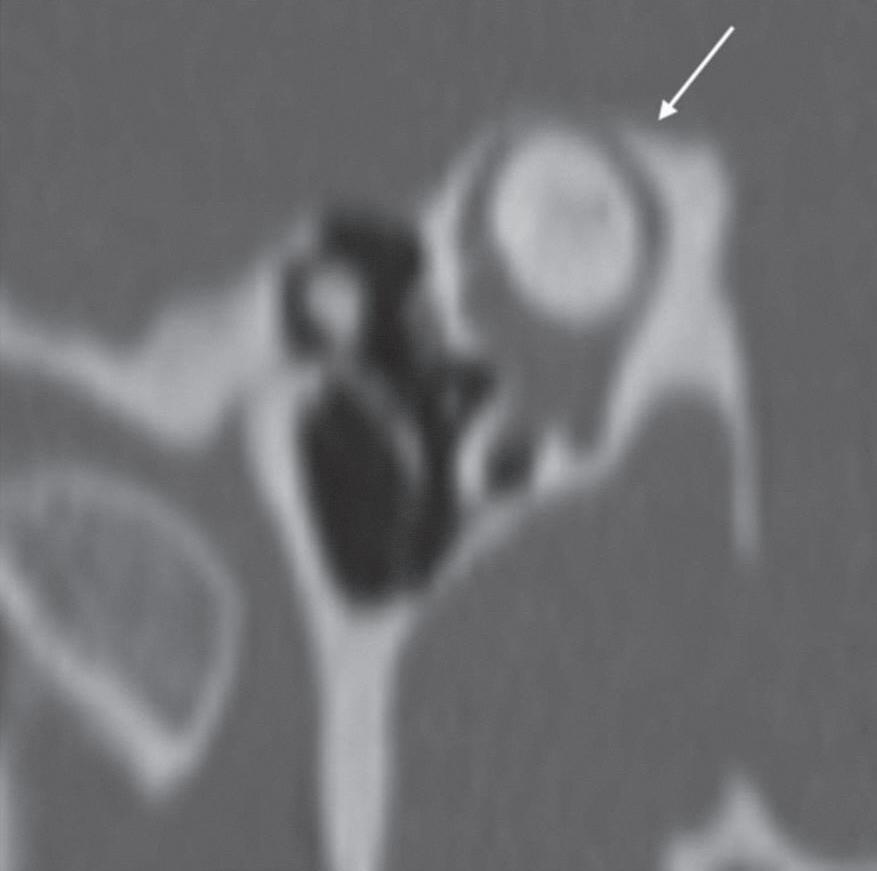

Fig. 1-5. Incidência de Poschl e Stenvers para avaliar o revestimento ósseo do canal semicircular superior (CSS). (a) TC em incidência de Poschl demonstrando porção superior do canal semicircular superior com o revestimento ósseo adequado (normal). (b) Incidência de Poschl com deiscência do CSS. (c) TC Stenvers: revestimento ósseo exíguo do canal semicircular superior. (d) TC incidência Poschl: revestimento ósseo exíguo do CSS.

1-6. TC 3D: Osso temporal normal, visão superior e lateral. TC 3D visão superior (a) e lateral (b) do osso temporal normal (setas).